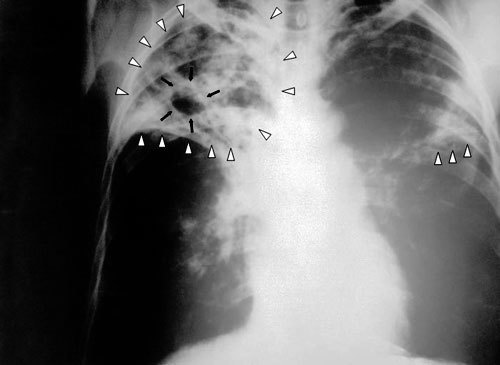

Гуманитарная организация "Международный медицинский корпус" подвела итоги работы на Северном Кавказе за 2009 год. Врачи отмечают, что в регионе растет заболеваемость туберкулезом и ВИЧ, а лечебно-профилактические учреждения в достаточном объеме отсутствуют.

Рост заболеваемости туберкулезом на Северном Кавказе практически самый высокий в России

"Рост заболеваемости туберкулезом на Северном Кавказе практически самый высокий в России. В Чечне как уже зарегистрированных, так и новых случаев больше, чем в любом другом регионе России за исключением тех, где находятся учреждения пенитенциарной системы, в частности, в некоторых регионах Сибири", - рассказал корреспонденту "Кавказского узла" руководитель российского отделения ММК Семен Расин.

По данным врачей, сегодня в Чечне около 5 000 зарегистрированных больных туберкулезом. По словам Семена Расина, официальные цифры заболеваемости отражают лишь часть реальности. "Уровень заболеваемости туберкулезом очень значительный, причем уровень его выявляемости крайне низок. Очень плохой уровень подготовки специалистов. Есть энтузиасты, которые пытаются что-то сделать. А вот квалифицированных специалистов на местах практически нет - никто не хочет ехать работать в Чечню", - сетует руководитель российского отделения ММК.

На вопрос, в чем причины роста числа людей, больных туберкулезом, Семен Расин отвечает так: "Во время войны в Чечне не было никаких лекарств вообще. Все больные, которые находились на лечении от туберкулеза, перестали его получать, заражая при этом остальных. Во-вторых, туберкулез - болезнь социальная, болезнь бедности. Уровень безработицы в Чечне достигает 70% населения, а безработица среди молодежи - 85%".